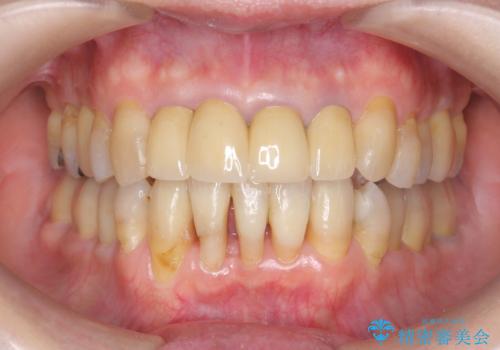

![[ インビザライン矯正 ] マウスピース矯正で治す、前歯のガタつきの症例 治療前](https://seimitsushinbi.jp/wp/wp-content/uploads/2022/02/324533f54aaa29eca08b0a9fdd3af7e2-500x350.jpg?v=1644473292)